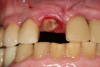

Figure 6 and Figure 7 depict a mature smile with many implant restorations. An analog impression was sent to the laboratory. The impression was scanned by the laboratory, a model was created virtually, and the implant dimensions and position were defined. The 3D surgical guide was fabricated (Figure 8), allowing the patient to receive his therapy swiftly and predictably. Tooth No. 8 was extracted, and the implant was placed and immediately loaded with an acrylic provisional treatment crown (Figure 9). The screw-retained treatment crown was fabricated in-office from a previously completed diagnostic wax-up.

Fig 9. Surgery day with immediately loaded implant and treatment crown.

Figure 9